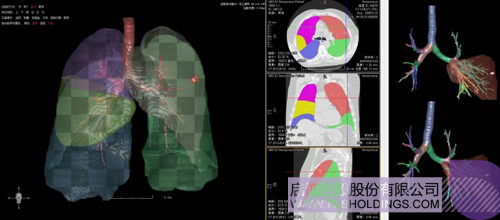

数字肺产品肺癌计算机辅助诊断

医疗影像智能分析是指运用人工智能技术、计算机视觉技术以及计算几何技术对医疗影像进行自动分析,帮助医生定位病症、分析、跟踪病情,并通过量化数据辅助医生做出诊断,目前其旗舰产品“数字肺”已经覆盖多种肺部疾病的早期检测、诊断、跟踪、术前规划等完整的医疗流程。在临床实践中,超过80%的医疗数据来自医疗影像,这些影像数据通常需要专业医生进行解读,工作的重复性高、效率偏低。如果能够运用智能影像分析技术,同时结合临床表现以及既往病例进行全面分析,那么就可以大幅度提升影像诊断效率和准确性,让专业医生的宝贵时间集中在复杂病情的诊断和治疗等环节。

数字肺——肺结节手术规划系统